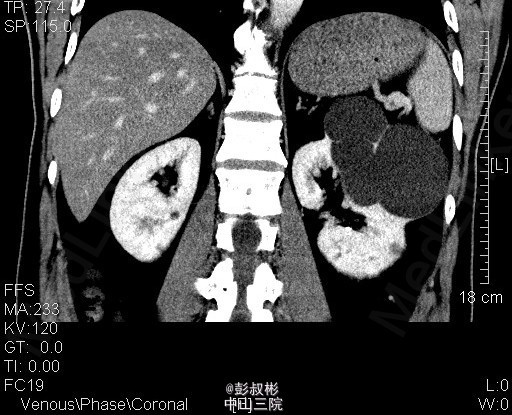

3、查体:腹稍膨隆,无压痛、反跳痛,未触及肿物,双肾区无红肿、隆起,无叩痛,双侧肋脊点、肋腰点无压痛。腹平软,双侧上中输尿管点无压痛,膀胱区无压痛。双侧腹股沟区未触及肿物。 4、CT:双肾多发囊肿,左肾囊肿较大,推压左侧肾盂肾盏。左肾小结石.轻度弥漫性脂肪肝

5、左肾囊肿 6、住院后完善相关检查,查血、尿常规,生化,凝血,心电图,胸片等未见明显异常。CT:双肾多发囊肿,左肾囊肿较大,推压左侧肾盂肾盏。左肾小结石.轻度弥漫性脂肪肝。经术前准备,行单孔腹腔镜下肾囊肿去顶术,手术顺利,术后予预防感染、营养支持等治疗,术后恢复较好,术后病理示:左肾囊肿。